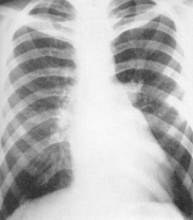

Imaginea radiologica a cordului si vaselor mari în pozitia posteroanterioara este aceea a unei opacitati de forma triunghiulara cu baza pe diafragm si vârful în sus. Marginile opacitatii cardiovasculare sunt reprezentate de trei arcuri în partea stânga, doua arcuri în partea dreapta, delimitate între ele prin depresiuni care sunt însemnate cu litere: D - pentru marginea dreapta, 656k105g S - pentru imaginea stânga.

Cordul verticalizat - se întâlneste la astenici, are axul longitudinal aproape vertical, vârful cordului apropiat de liania mediana, arcul inferior stâng si drept simetrice, limita între arcurile marginii stângi stearsa.